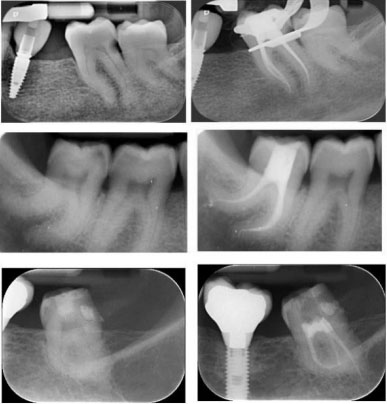

• Anatomia endodontica: interpretazione radiografica e apertura di camera, sondaggio manuale.

• Determinazione lunghezza di lavoro e uso del localizzatore elettronico d’apice.

• Eziopatogenesi, quadro clinico e diagnosi delle patologie endodontiche; lesioni endoparodontali; fratture e sindrome del dente incrinato; pronto soccorso endodontico e uso dei farmaci in endodonzia.

• L’otturazione canalare: tecnica laterale e verticale, tecnica Microseal; nuove tecniche di otturazione con materiali bioceramici;

• Discussione dei casi e delle radiografie.

• Analisi dei casi clinici con assegnazione degli stessi.

• Esecuzione di cure endodontiche sotto la sorveglianza del tutor.